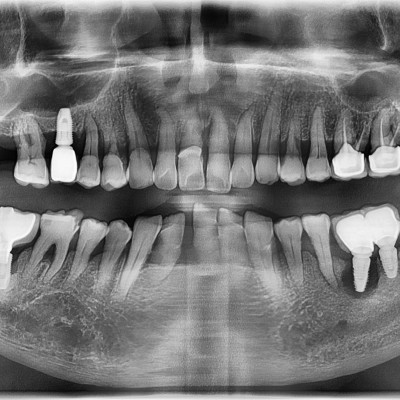

임플란트 재수술 #25.26.27 타원 임플란트 제거 후 임플란트 재식립+치조골 이식술 시행하였습니다.